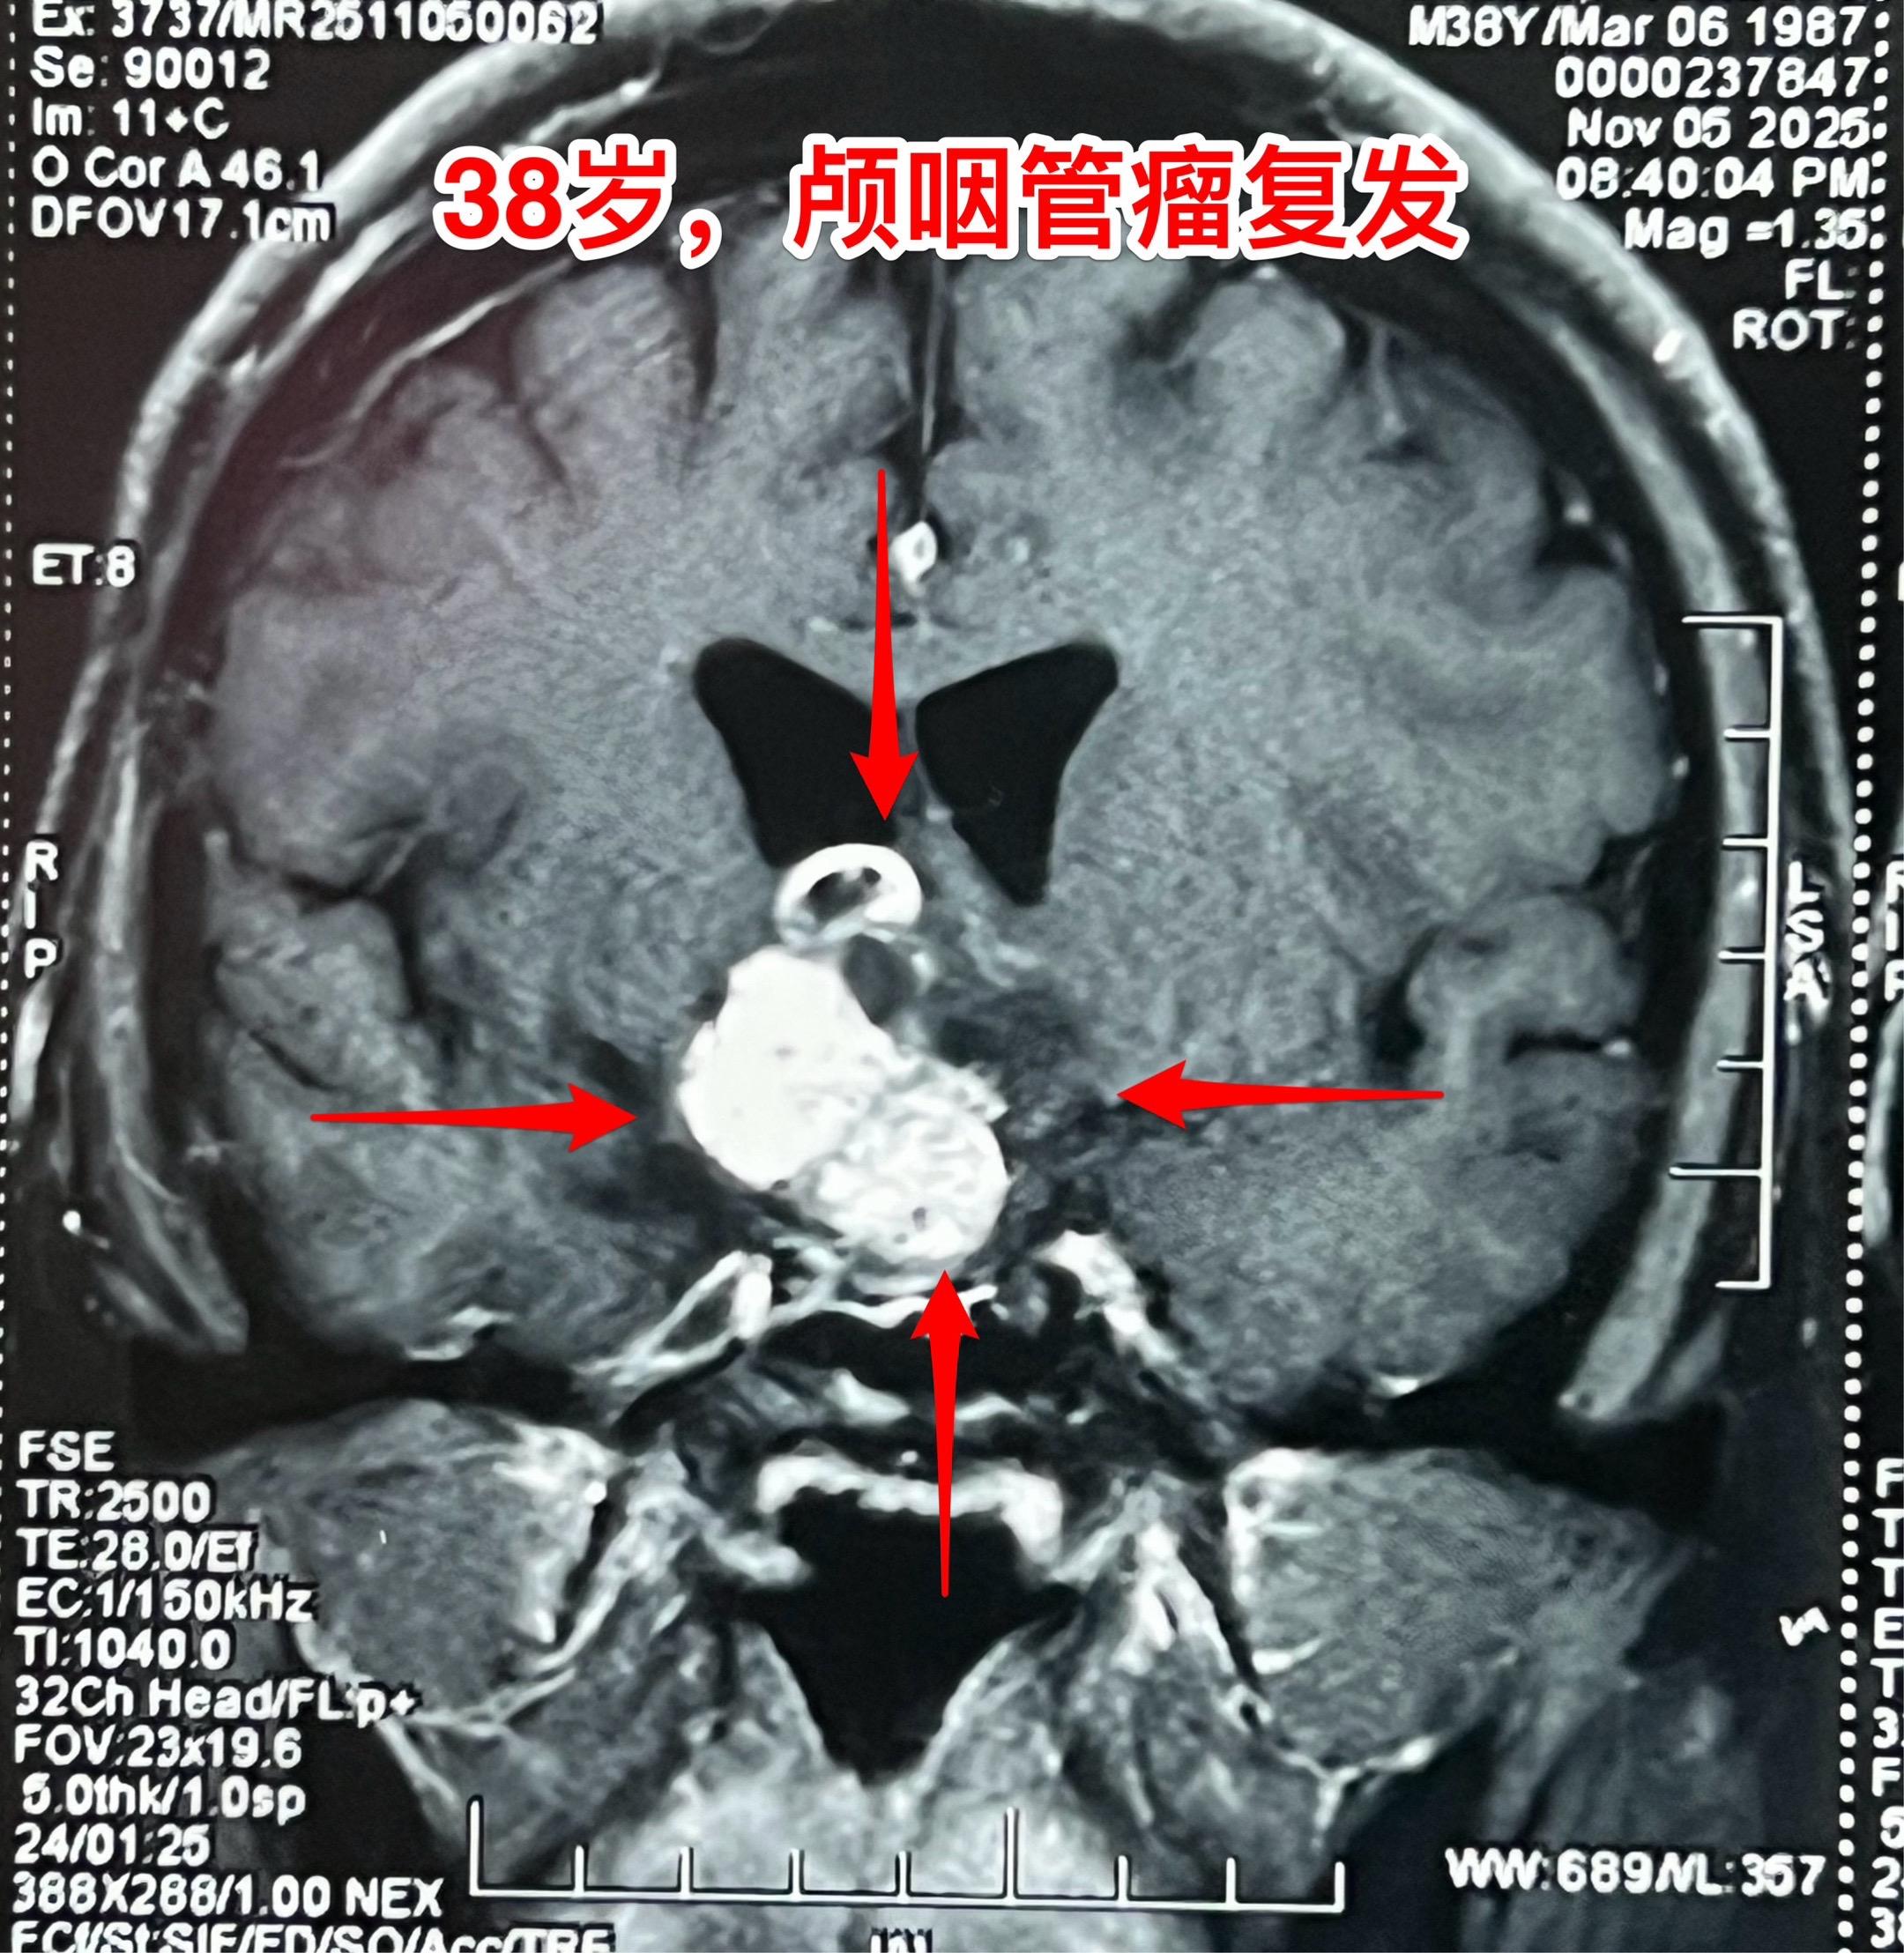

多次治疗后又复发的颅咽管瘤-不要轻易放弃。38岁福建男性,颅咽管瘤复发。 十年前因颅咽管瘤导致右眼几乎失明、右侧肢体无力,在上海行开颅手术切除颅咽管瘤,术后右眼完全失明。随后放疗一个月。2023年因颅咽管瘤复发在福建省某医院行经鼻内镜手术切除复发颅咽管瘤,肿瘤有残留。2025年5月仅有视力的左眼出现又视力下降,磁共振显示颅咽管瘤复发了,体积在增大。 病人患病十年,仍是未婚状态,家人的照顾是非常周到的。两个姐姐、两个妹妹和父母都在极力照顾他,这次得知肿瘤复发了,找到我,还是希